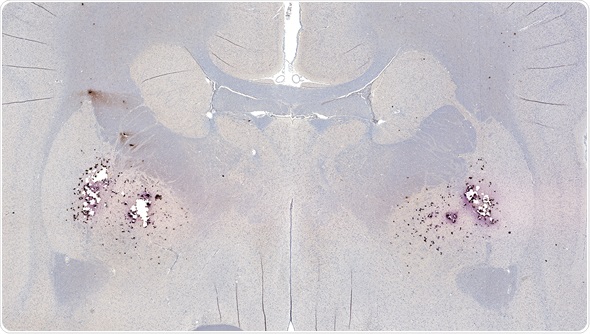

Amyloid plaques consist of dense, mostly insoluble clumps in the spaces between the nerve cells in the brain tissue. The plaques are made up of beta-amyloid, which is a protein peptide or fragment that appears to have toxic effects on the function of the surrounding brain cells.

Image Copyright: vetpathologist, Image ID: 73918573 via www.shutterstock.com

Over time, some individuals develop amyloid plaques in the central nervous system as they age. There are some regions of the brain that are particularly prone to the development of the plaques, such as in the hippocampus. The hippocampus is important for the processing of memories from short-term to long-term and damages in this area of the brain is associated with symptoms of Alzheimer’s disease.